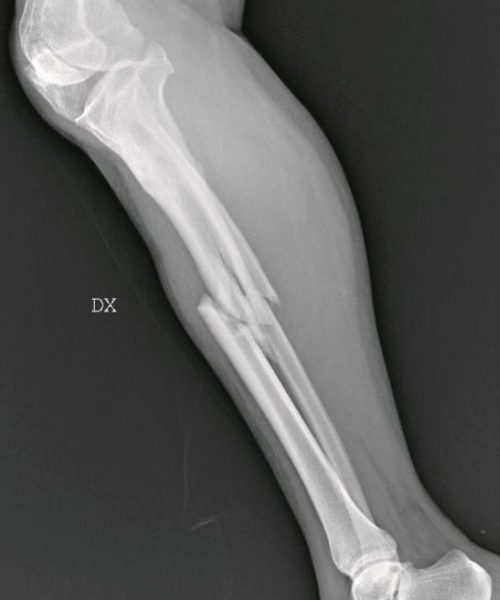

Σπασμένη κνήμη/repubblica.it

Όπως σημειώνει η χειρουργός, καθημερινά καλούνται να αντιμετωπίσουν «σπασμένα οστά σε μύτη, χέρια, πόδια, πληγές από μαχαιριές, εγκαύματα, μελανιές και άλλα σημάδια στραγγαλισμού», ενώ σημειώνει πως έχει δεχθεί ασθενή ακόμη και με μαχαίρι στην πλάτη, που όμως το περιστατικό δηλώθηκε ως «ατύχημα» στο νοσοκομείο.